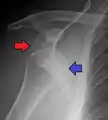

Anterior dislocation of the left shoulder.

X-ray at left shows anterior dislocation in a young man. X-ray at right shows the same shoulder after reduction and internal rotation, revealing a Bankart lesion and a Hill-Sachs lesion.

In over 95% of shoulder dislocations, the humerus is displaced anteriorly.[7] In most of those, the head of the humerus comes to rest under the coracoid process, referred to as sub-coracoid dislocation. Sub-glenoid, subclavicular, and, very rarely, intrathoracic or retroperitoneal dislocations may also occur.[8]

Anterior dislocations are usually caused by a direct blow to, or fall on, an outstretched arm. The person typically holds his/her arm externally rotated and slightly abducted.